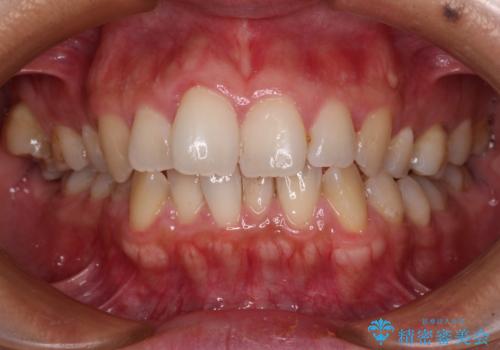

前歯のデコボコを改善 インビザラインの矯正治療

- 前歯のデコボコを治したいとのことで来院された患者様です。

上下顎ともに歯列全体の後方移動とIPR(歯と歯の間を削る)によってデコボコが解消するように設計し、インビザラインにより治療を行うこととしました。